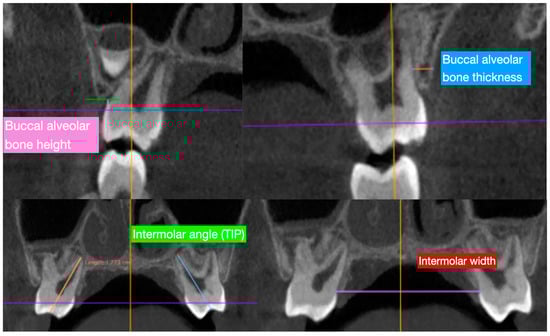

- Buccal alveolar bone thickness (BT), defined as the distance between the buccal root surface and the outer border of the alveolar bone, along a horizontal line passing through the furcation;

- Buccal alveolar bone height (BH), defined as the distance between the buccal or mesio-buccal cusp tip and the buccal alveolar bone crest;

- Inter-dental angle (TIP), represented by the angle between the right and left axes of the upper molars (6-6) and deciduous molars (E-E), determined by connecting the central fossa and the apex of the palatal root; and

- Inter-molar width (IW), defined as the upper inter-molar (6-6) and deciduous molar (E-E) distance between the mesio-buccal cusp tips.